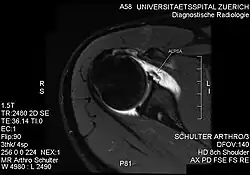

PD-weighted MRI with fat saturation of the shoulder showing an ALPSA lesion

An ALPSA (anterior labral periosteal sleeve avulsion) lesion is an injury at the front of the shoulder associated with shoulder dislocation.[1]